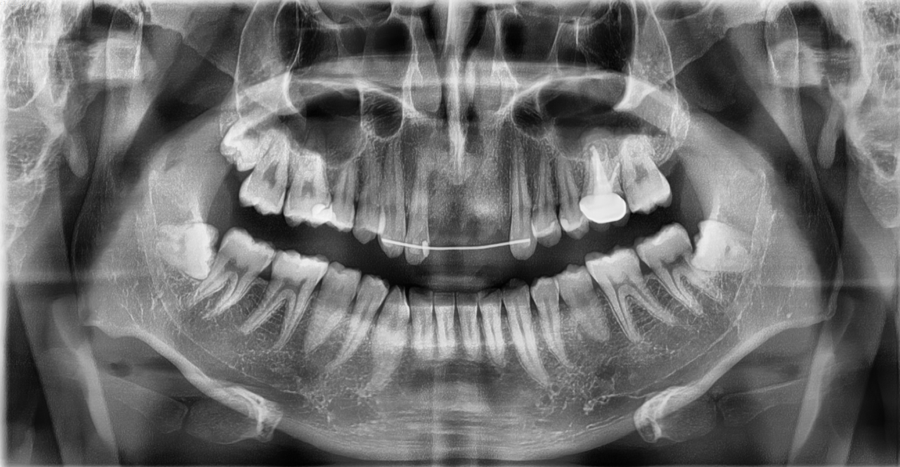

교통사고 충격으로 앞니가 완전히 빠진 상태로

내원하신 환자분의 엑스레이입니다.

치아를 지지하는 잇몸과 주변 구조를 안정시키기 위해

와이어를 이용한 임시 고정 치료를 먼저 진행한 사례입니다.